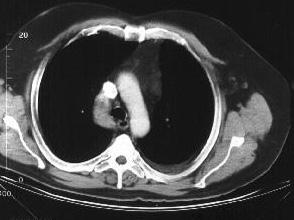

问题 中年男性,间断性腰背痛4个月,突发左下肢全肢水肿,小腿有张力性水泡,水肿累积会阴部,常规胸腹部CT扫描如图所示,你认为哪些征像及结论正确 ( )

选项 A、奇静脉变细 B、正常CT表现 C、下腔静脉变细 D、奇静脉增粗 E、下腔静脉缺如

答案 DE